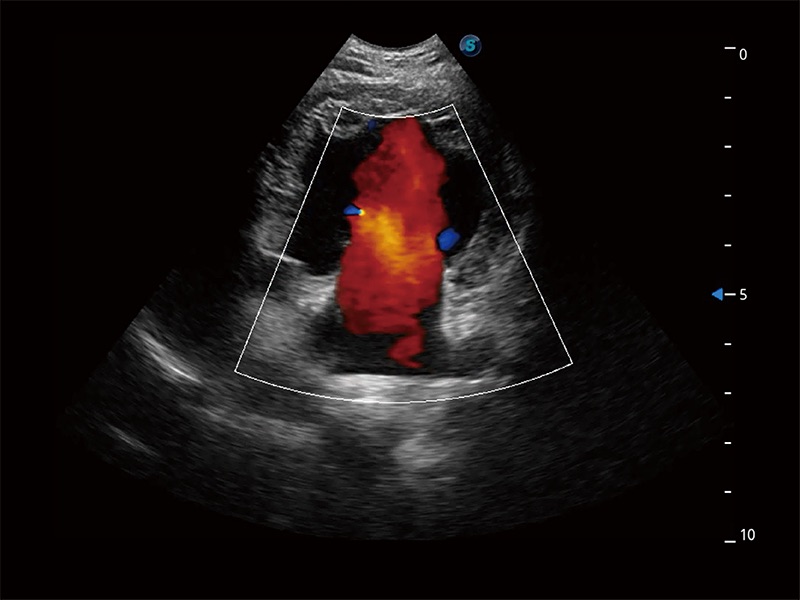

(犬)胎儿主动脉弓立体血流

• Bright Flow 立体血流成像

在传统二维血流成像的基础上,呈现血流的立体感,具有动感的生命力之美。即便是微小的血管也能轻松应对,提高了血流的视觉敏感性。